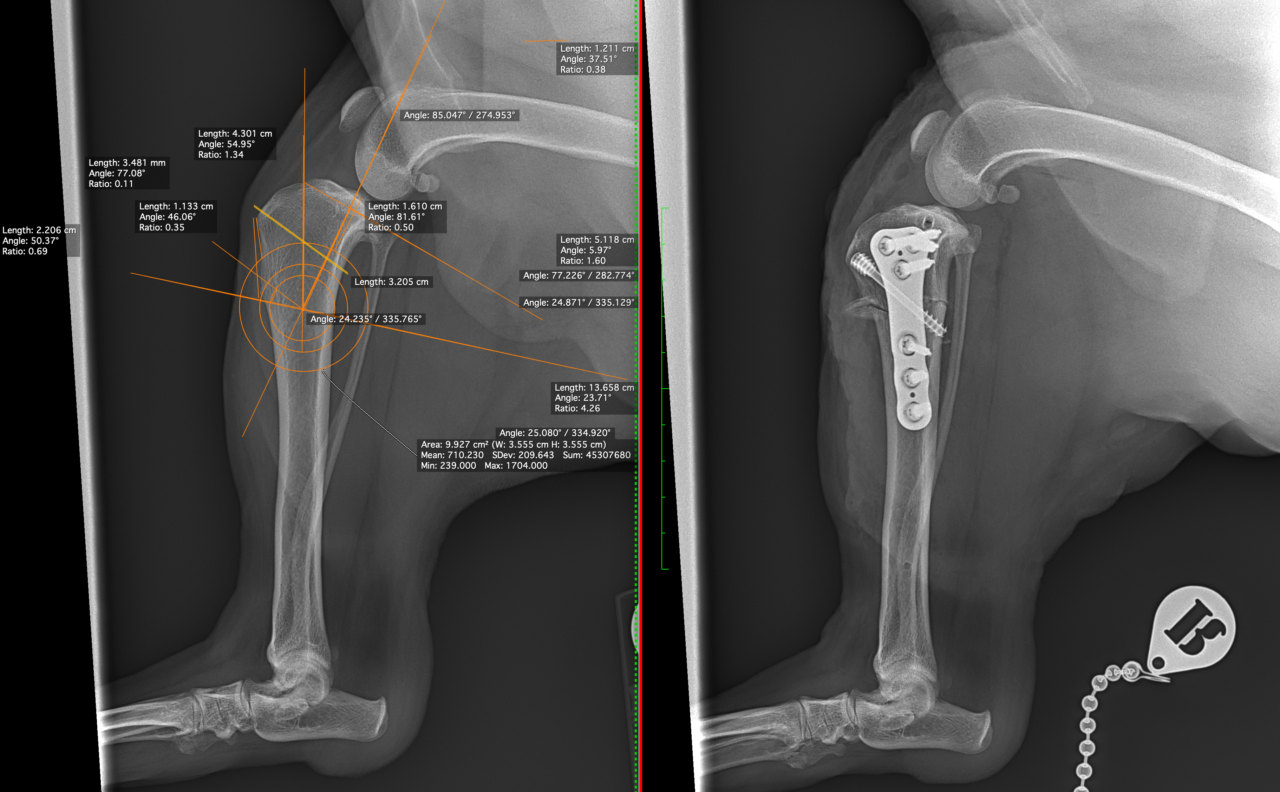

中型サイズのワンコの前十字靭帯断裂にCBLOの依頼です。ドロアーサイン陽性、脛骨圧迫試験陽性、脛骨ピボット圧迫試験陰性、慢性のCrCLDに急性の半月板損傷が併発し、今回の跛行が顕著になった可能性があります。2,7 CCWO PlateとCompression Bone Screwを用いてCBLOを実施しています。しばらくは安静が必要です。